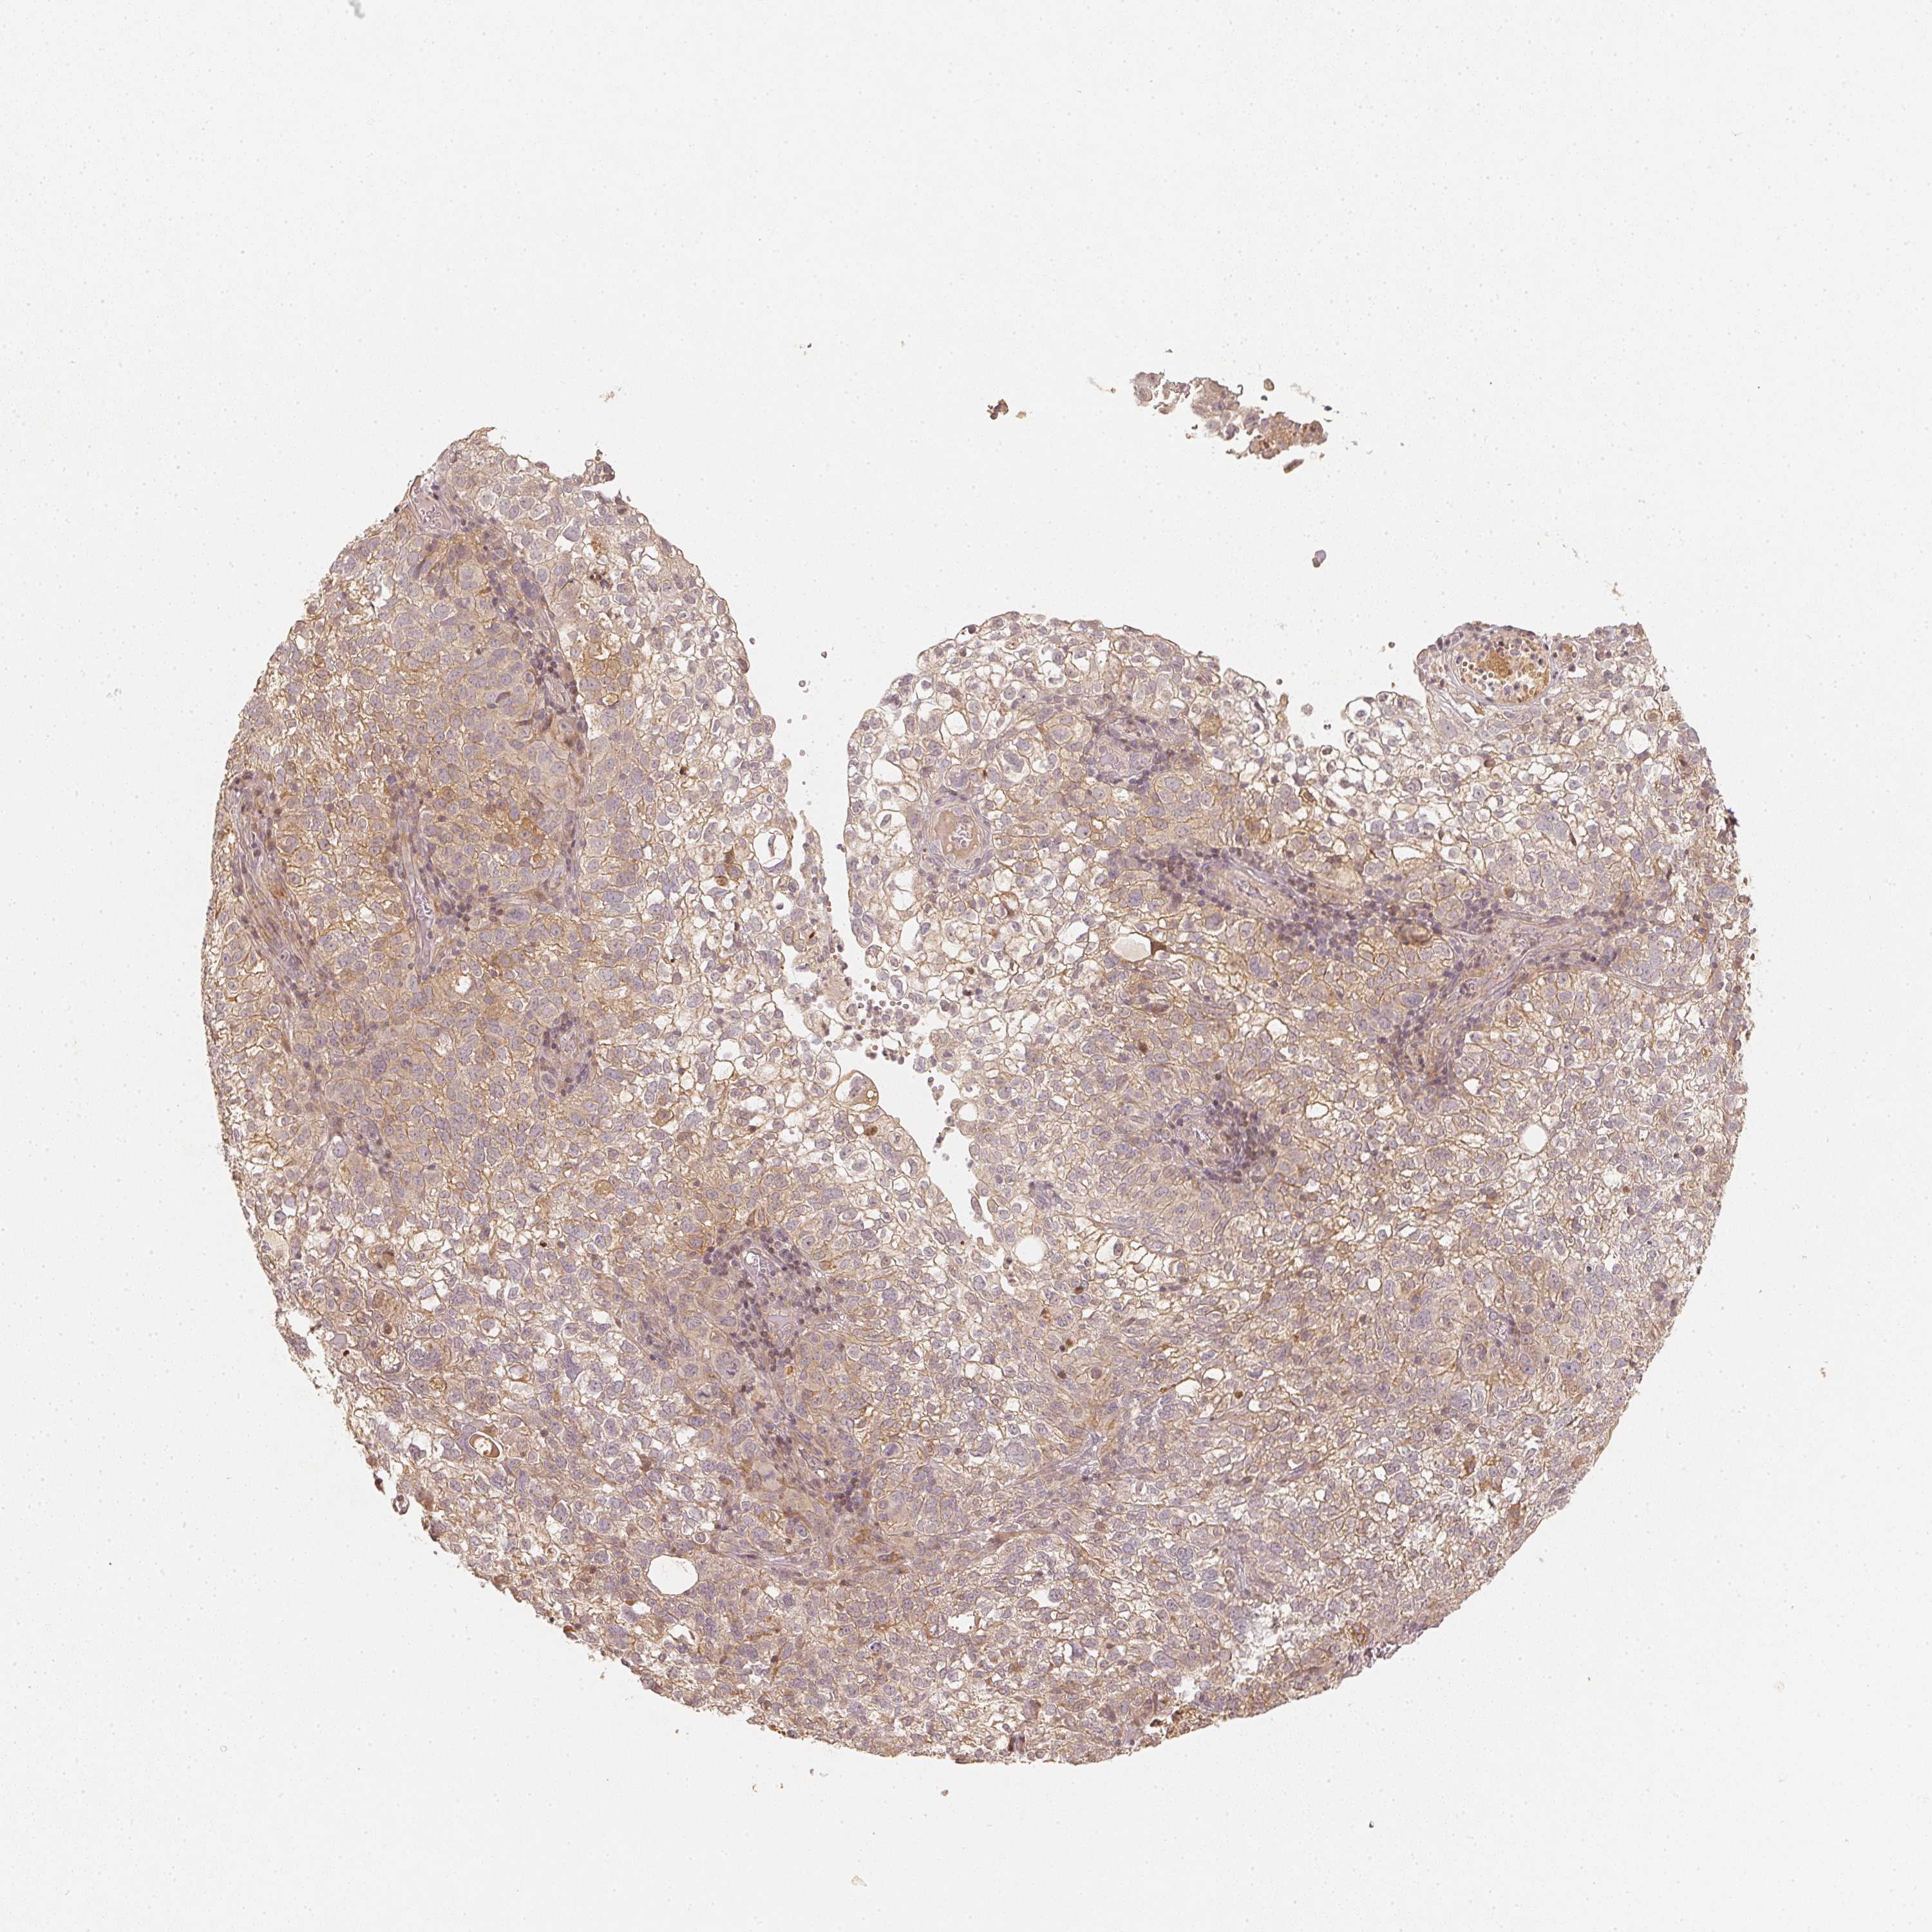

CERVICAL CANCER - Protein expressioni

A mouse-over function shows sample information and annotation data. Click on an image to view it in a full screen mode. Samples can be filtered based on level of antibody staining by selecting one or several of the following categories: high, medium, low and not detected. The assay and annotation is described here.

Note that samples used for immunohistochemistry by the Human Protein Atlas do not correspond to samples in the TCGA dataset.

Antibody stainingi

Antibody staining in the annotated cell types in the current human tissue is reported as not detected, low, medium, or high, based on conventional immunohistochemistry profiling in selected tissues. This score is based on the combination of the staining intensity and fraction of stained cells.

Each image is clickable and will lead to virtual microscopy that enables deeper exploration of all samples and also displays staining intensity scores, fraction scores and subcellular localization as well as patient and tissue information for each sample.

Antibody CAB068501

Staining

High

Medium

Low

Not detected

Intensity

Strong

Moderate

Weak

Negative

Quantity

>75%

75%-25%

<25%

None

Location

Nuclear

Cytoplasmic/membranous

Cytoplasmic/membranous,nuclear

Squamous cell carcinoma, NOS

Adenocarcinoma, NOS